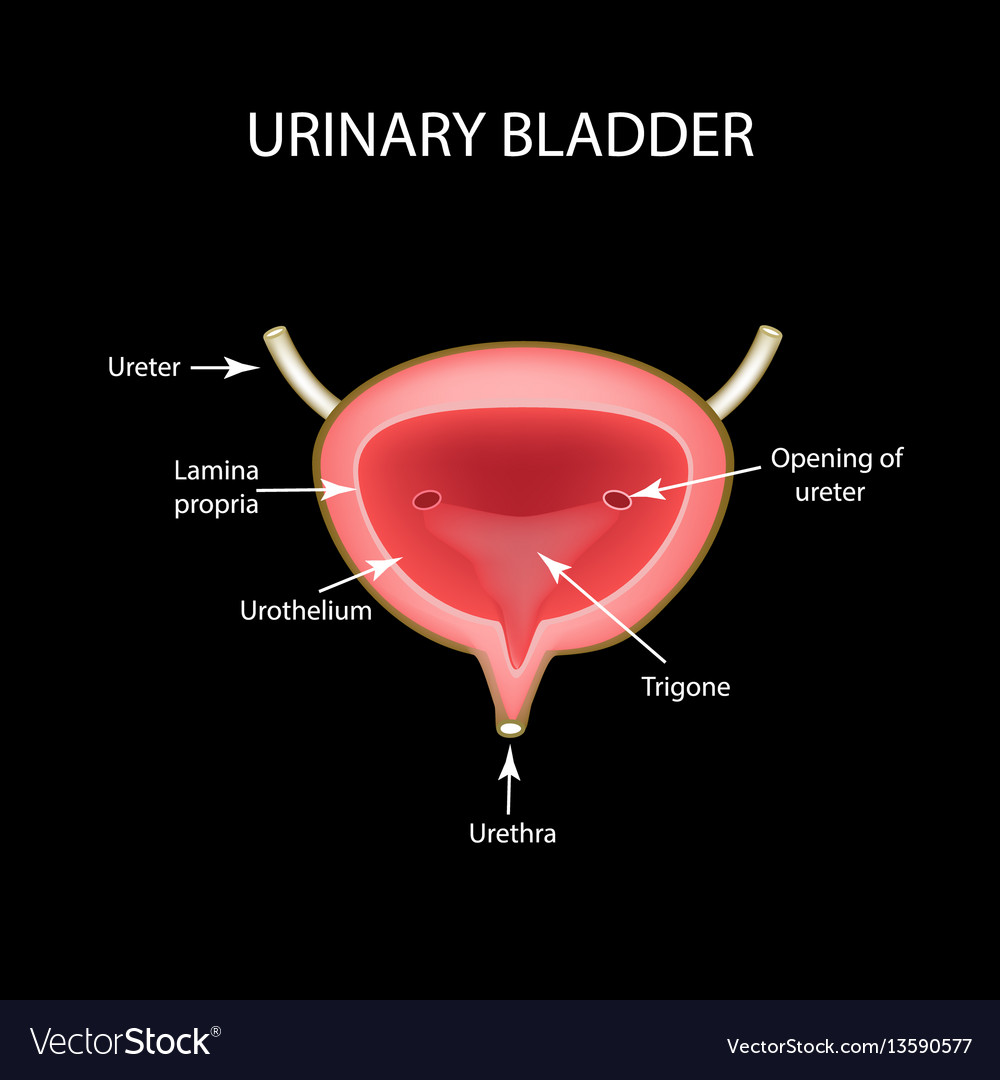

Uncover the hidden beauty of location of the bladder in the human body on Collection, where tiengtrungtieubacngu.edu.vn has gathered a remarkable set of images. The exploration continues in the details.

location of the bladder in the human body

Posts: location of the bladder in the human body